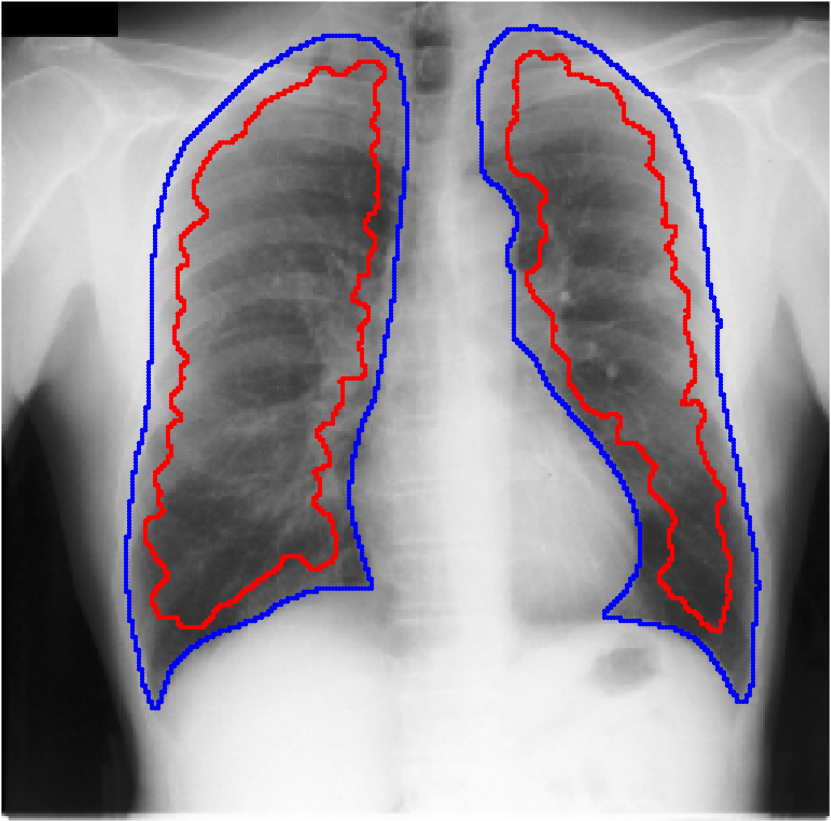

Table 1 shows the segmentation results of different methods with synthetic noisy label settings on JSRT , ISIC 2017 and Brats 2020 dataset. Note that QAM cannot be applied to Brats 2020 dataset because their network is designed for 2D only. We compare DICE score (DSC) on testing sets (against the clean labels). For each setting, we train 5 different models, and report the mean DSC and standard deviation. In and , where biases show up in noisy labels, the proposed method outperforms the baselines by a big leap in total case. The compared methods, however, only work when little bias is included, like . is equivalent to setting in our Markov model, resulting in . We also test the proposed method on real-world label noise, results shows in Table 2. Figure 5 shows examples of label correction results. We provide more qualitative results in the Appendix A.4.

A.4 Qualitative Results

We provide qualitative results for prediction on test images in Fig. A.6 and Fig. A.7 as two sub parts. We also show the label correction on training images in Fig. A.5.